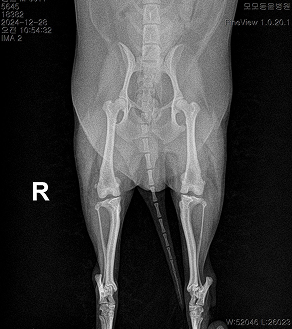

BEFORE

AFTER